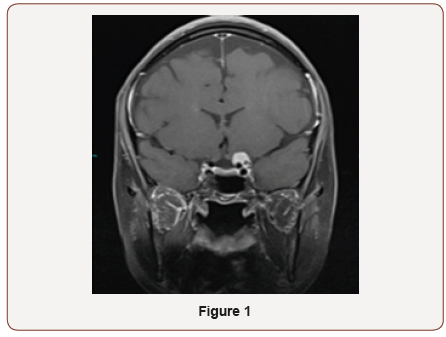

The patient is a 39-year-old female who was referred to neuroophthalmology office on November 2018 for the optic atrophy of left eye. She had noticed vision less in the left eye when she went to DMV for renewal of her license. She was not aware of the duration of vision loss. There was no history of pain with eye movement, trauma to the eye, infectious, and or inflammatory disease. She denied headaches, diplopia, numbness or tingling, and low back pain. Her past medical and surgery history was not significant. In eye exam, her vision was 20/25 on right and 20/150 left eye. Color vision was 11/11 in right and 1/11 in left eye. She had RAPD in left eye. Visual field of the right eye was normal. She was not able to do visual field on the left side. OCT optic nerve showed mild RNFL thinning on the left eye. MRI brain and orbit showed an enhancing mass impressing on the posterior aspect of the left optic nerve showing a slight dural tail measuring 13.1x11.1x12.2 mm, consistent with meningioma. The mass encases left internal artery. She was referred to neurosurgeon for tumor resection. She gained back some of her vision immediately after surgery. The patient came back for follow up on December 2018. Her vision was 20/20 in both eyes and color vision on left eye was improved to 5/11 (Figure 1,2).